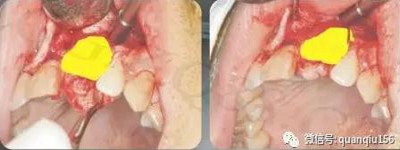

四、種植牙植骨第四個(gè)步驟:植入人工骨粉,蓋口腔修復(fù)膜,如骨膜完整也可以不蓋膜。

五、種植牙植骨第五個(gè)步驟:如果同期種植,沿齦頰溝切口向腭側(cè)分離翻轉(zhuǎn)粘骨膜瓣,顯露牙槽嵴骨面,在設(shè)計(jì)的位置上逐級(jí)鉆孔,最后將種植體旋入就位。術(shù)前骨高度嚴(yán)重不足的也可以半年后種植。